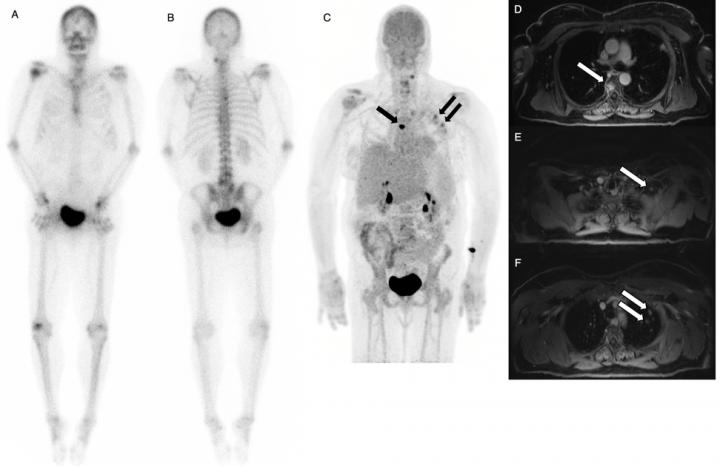

DENVER, Colo. - Simultaneous injections of the radiopharmaceuticals fluorine-18 fluorodeoxyglucose ( 18 F-FDG) and 18 F-sodium fluoride ( 18 F-NaF) followed by quantitative scanning significantly improves image quality and detection of bone metastases at a lower dose, according to research presented at the 2017 Annual Meeting of the Society of Nuclear Medicine and Molecular Imaging (SNMMI).

Dual-agent PET/MR is further supported by time of flight, a quantitative feature of modern PET image reconstruction that approximates the position where photons are created as radioactive agents decay, which translates into finer image quality.

After injection, scientists performed PET/ MRI scans with time of flight capability and compared the results with conventional technetium 99 m-methyl diphosphonate ( 99 mTc MDP) bone scintigraphy. Results of the study showed improved detection of prostate and breast cancer that had metastasized to bone. Dual-agent PET/MR pointed to bone metastases in 22 patients who were also found positive for metastases with conventional bone scan. In addition, PET/MR detected more bone metastases in 14 patients when compared to the conventional bone scan, which caught only one lesion that was not detected by PET/MR.

Researchers concluded that PET/MR found a greater extent of metastases and, as an added benefit, significantly reduced the required radiation dose from the injected agents--80 percent less from 18 F-NaF and 67 percent less from 18 F-FDG.